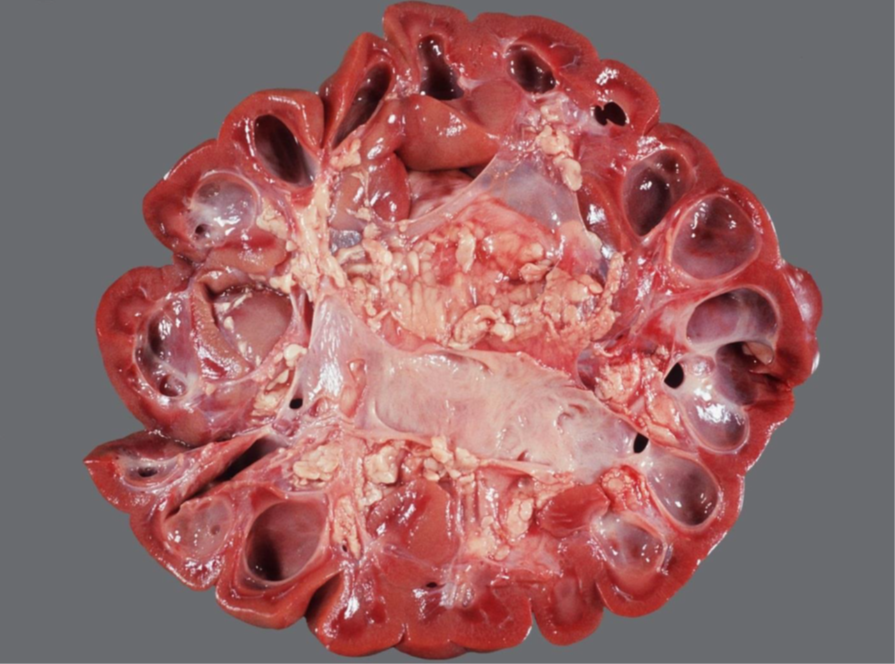

Rind, Niere: Hochgradige chronische diffuse Amyloidose der Niere (Amyloidnephrose)

Nierenrinde hellbeige

Oberflächefeingranuliert, speckig

die Renculi erscheinen prominent

derbe Konsistenz

- Amyloid ist ein fibrilläres Protein, in dem die β-Faltblattstruktur dominiert vermehrter Anfall durch

gesteigerte Synthese oder unvollständige Proteolyse

- Amyloidnephosen v.a. bei Rind, Hund, Katze

AA Amyloid:

- In der Niere meist reaktive systemische Amyloidose: chronischen Entzündungsprozessen ->

gesteigerte Synthese von Serum-Amyloid-A-Protein (Akute-Phase-Protein) durch Hepatozyten ->

Abgabe ins Blut sekundäre Ablagerung von AA-Amyloid vor allem in den Glomeruli

- Familiäre Amyloidose (z.B. Shar-Pei, Abessinerkatze)

AL-Amyloid:

- Selten, z.B. beim Multiplen Myelom

- Beeinträchtigung der glomerulären Filtration durch vermehrte Durchlässigkeit -> Proteinurie, nephrotisches Syndrom

- Differentialdiagnose: Lymphom